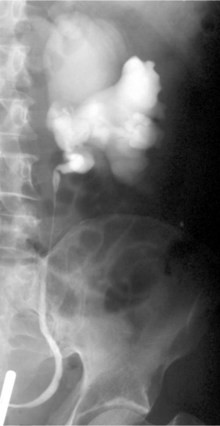

Before the advent of cross-sectional imaging, radiologic diagnosis relied upon imaging not the disease process itself but its secondary effects on the ureters. The classic radiologic findings included medial deviation of extrinsically compressed ureters with hydronephrosis. Medial deviation is a nonspecific finding, because it has been demonstrated in up to 18% of normal subjects (Saldino and Palubinskas, 1972). Hydronephrosis is typically demonstrated on ultrasonography, and there may also be a smooth, well-demarcated, hypoechoic or isoechoic mass anterior to the lumbar or sacral spine (Amis, 1991). Retrograde pyelography typically demonstrates hydronephrosis, with medially deviated and segmentally narrowed ureters without filling defects (Fig. 40–10). Currently, cross-sectional imaging with CT or MRI is the modality of choice for evaluating patients with suspected retroperitoneal fibrosis. Both modalities have been demonstrated to delineate accurately the extent of the disease when correlated with surgical exploration (Mulligan et al, 1989). CT typically reveals a well-demarcated retroperitoneal mass, isodense with muscle on unenhanced studies (Fig. 40–11) (Vivas et al, 2000). It typically surrounds the lower abdominal aorta, inferior vena cava, and iliac vessels—frequently enveloping the ureters. In contrast, masses secondary to malignancy usually displace the aorta anteriorly and the ureters laterally. Variable degrees of contrast enhancement may be seen, typically more pronounced earlier in the course of the disease when the presumably more-immature plaque has increased vascularity (Amis, 1991). Some have advocated noncontrast multidetector CT imaging combined with antegrade CT pyelography for evaluation, because it can define the fibrotic process and the level and degree of ureteral obstruction without administration of intravenous contrast material (Ghersin et al, 2004). However, the invasive nature of this diagnostic approach limits its applicability.

Figure 40–10 Retrograde pyelogram performed in a patient with retroperitoneal fibrosis. Note evenly narrowed midureteral segment with proximal hydronephrosis.

(Courtesy of Dr. Ronald Zagoria.)